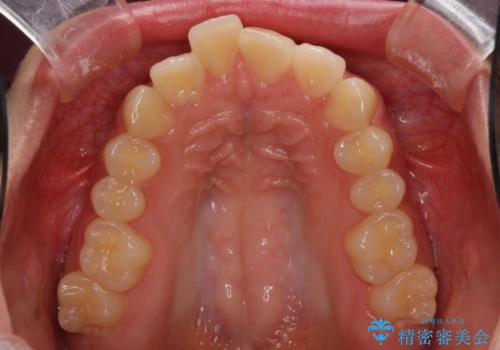

就職前にきれいな歯並びにしたい 大学生のインビザライン矯正

- 就職するまでに歯並びをきれいにしたいとのことで来院された患者様です。

前歯の叢生を気にしていましたが、極力突出感を改善できるようにすることとし、インビザラインにて矯正治療を行うこととしました。

改善の期待できない口元の突出感改善を希望されたため、いたずらに治療期間が延びましたが、きっちりと仕上がりました。